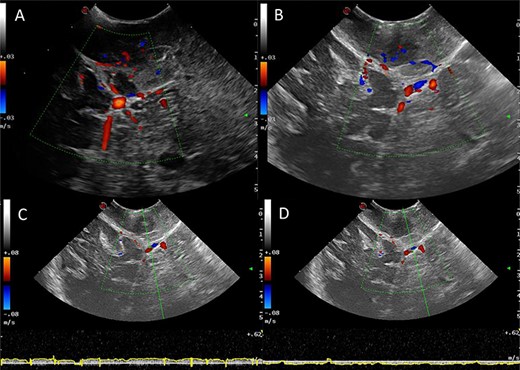

Power and colour Doppler were used throughout to obtain real-time information about the location and function of dural venous sinuses. Blood flow was preserved in the sinuses and, as we debulked the tumour, we were able to demonstrate bi-directional flow within the sinuses (Fig. 3). This suggested resolution of venous obstruction and indicated the dural venous sinuses had regained their functionality. Medially tumour was found invading the torcula and right transverse sinus, and a decision was made to leave the residual tumour and to preserve the sinuses (Fig. 4). We achieved a Simpson Grade 4 resection without any intraoperative complications.

Correlation of US appearance and gross anatomy; (A and B) intraoperative picture of the surgical field at the end of resection; (C and D) final US assessment—B-mode (C) and duplex (D); 1, ipsilateral occipital lobe; 2, ipsilateral cerebellar hemisphere; 3, strip of bone on top of the transverse sinus; 4, supratentorial resection cavity; 5, infratentorial resection cavity; 6, torcular; 7, supra-infratentorial communication of the tumour via the tentorium; 8, straight sinus; 9, contralateral occipital lobe; 10, falx cerebri; 11, tentorium.